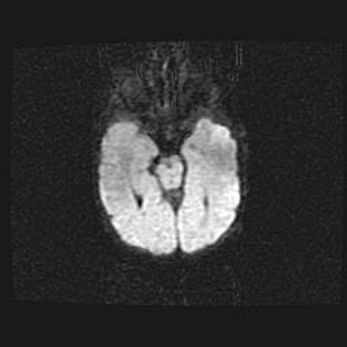

Лейкомаляция с кистозно-глиозной дегенерацией головного мозга.

Возраст: 2 месяца 25 дней

Вес: 6400 г

Окружность головы: 40 см

Срок гестации: 41 неделя

Лейкомаляцию относят к ишемически-гипоксическим повреждениям головного мозга, диагностируемым у новорожденных. При лейкомаляции в головном мозге обнаруживают очаги некроза, возникшие после тяжелой гипоксии и нарушения кровотока. В процессе морфогенеза очаги проходят три стадии: 1) развития некроза, 2) резорбции и 3) формирования глиозного рубца или кисты. Перивентрикулярная лейкомаляция (ПЛ) встречается примерно в 12% случаев среди новорожденных, обычно – у недоношенных детей, причем, частота ее зависит от массы, с которой младенец появился на свет. Наибольшее число малышей страдает лейкомаляцией, если масса при рождении 1500-2500 г.